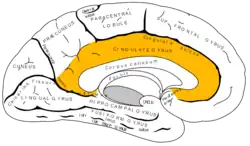

Meduální povrch mozkové hemisféry. SAgitální pohled.